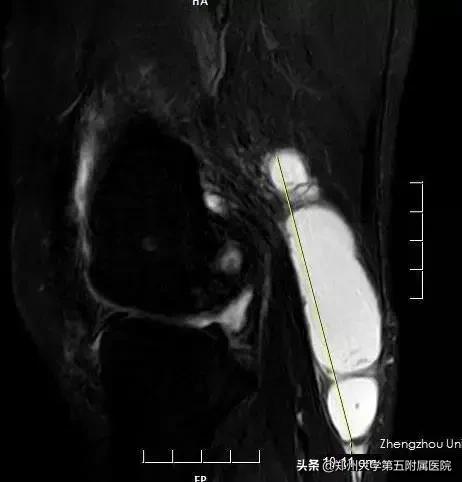

▲ 术前MRI检查巨大囊肿

杨女士经病友介绍郑州大学五附院骨外科*明徐**杰副主任擅长微创处理关节疾患,立即前来就诊。*明徐**杰副主任热情接待患者,并安排她入院,指示管床医师张鹏飞尽快完善检查。磁共振检查提示杨女士右侧膝关节不但存在巨大囊肿,同时合并严重的骨关节炎、半月板损伤。而且左膝恢复较差的原因是出现了慢性滑膜炎,上次手术对骨关节炎未能有效处理。*明徐**杰副主任仔细阅片,结合查体,并请示科主任张立贵主任医师。在张主任的准确判断和技术指导下,建议为患者右膝实施“关节镜下关节清理+囊肿切除手术”,并同时为左膝进行“关节镜下翻修术”。患者对骨外科团队非常信任,同意立即手术。